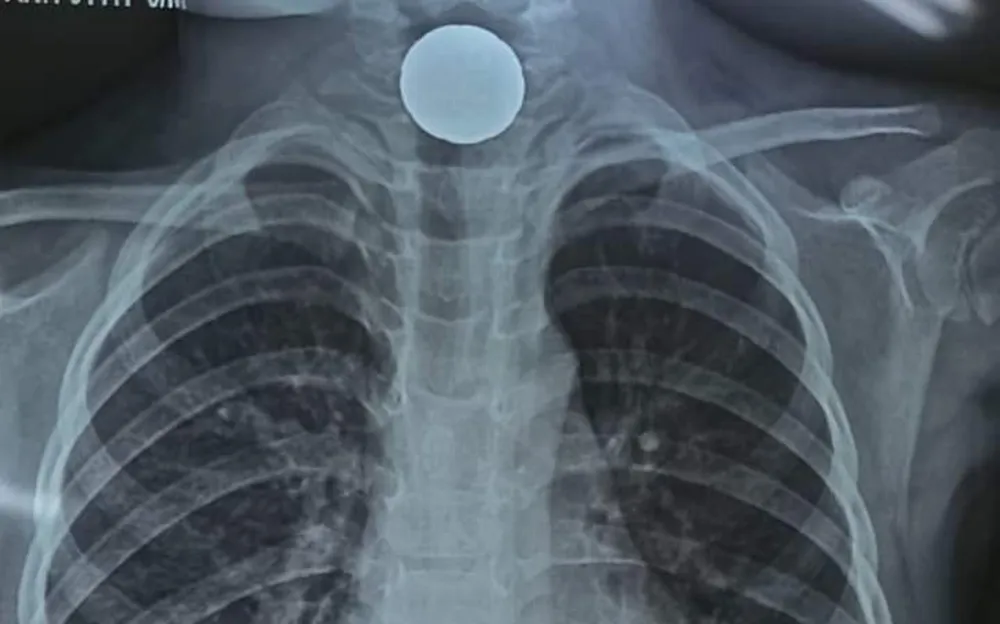

Qua kiểm tra và hội chẩn, các bác sĩ xác định A. bị dị vật là một đồng xu kẹt tại cơ thắt thực quản trên (rất gần đường thở). Bệnh nhân được chỉ định nội soi gắp dị vật.

![]() |

| Hình ảnh đồng xu mắc tại thực quản qua phim chụp X.Quang |